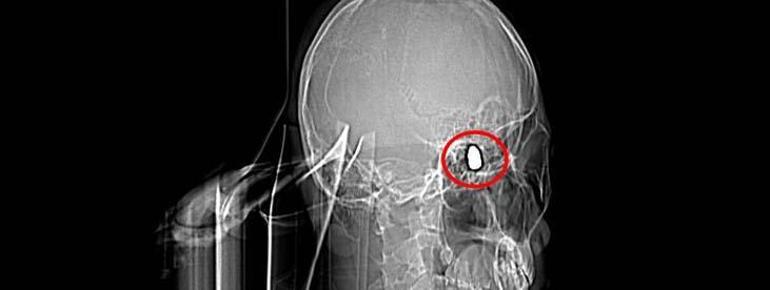

Olay, 5 Kasım 2023’te Bahçelievler Mahallesi 1624’üncü Sokak’ta meydana geldi. Arkadaşları ve ağabeyiyle maça gitmek için konutundan çıkan Yusuf Emre Özbek, birlikte fotoğraf çektirdikten çabucak sonra yere yığıldı. Etraftakilerin hastaneye götürdüğü Yusuf’un çekilen röntgeninde, başında mermi çekirdeği olduğu tespit edildi.

4 gün ağır bakım, 4 gün de serviste tedavi gören Yusuf’un başındaki mermi için tabipler, riskli bölgede olduğu gerekçesiyle müdahale etmedi. Nizamlı olarak denetim edilen Yusuf’ta konuşma zahmeti ve sağ el ve parmaklarında zayıflık belirtileri ortaya çıkınca, fizik tedavi süreci başladı.